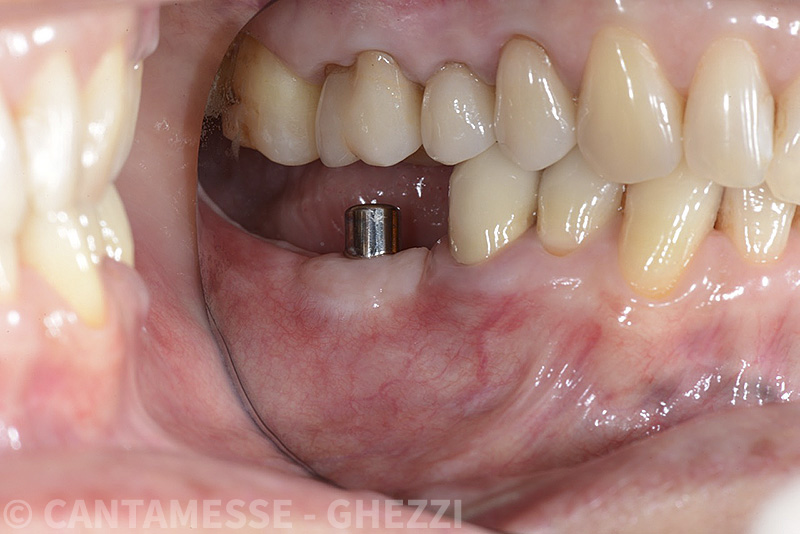

Vengono utilizzati 2 tipi di provvisori: il primo, cementato ai denti vicini, viene utilizzato dal momento dell’estrazione del dente fino ad impianto osteointegrato (circa 6 mesi); il secondo, avvitato direttamente all’impianto, ha una funzione di prova estetica ma soprattutto di guida per la maturazione dei tessuti gengivali peri-implantari portandoli verso la maturazione completa prima di posizionare la corona finale in disilicato di litio.